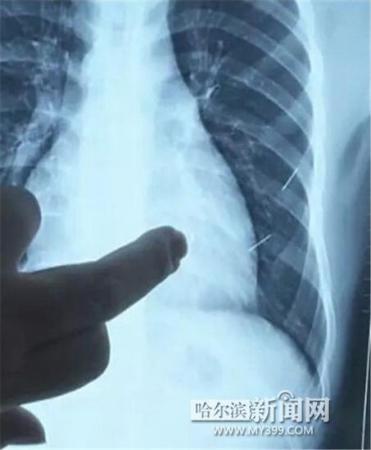

醫(yī)生指出X光片上的針狀物

昨日上午,記者在哈醫(yī)大二院第八住院部心外三病房找到了躺在病床上痛苦不堪的董立仁,家屬正在他身旁不斷安慰著他。見記者前來,董立仁母親李百燕拿出一張X光片,上面可以清晰地看到胸腔內(nèi)一共有4根針狀物,其中一根在心臟部位,兩根在胸腔壁上,還有一根在腹腔壁上。

心外三病房董立仁的主治醫(yī)生告訴記者,董立仁送到醫(yī)院時病情很危險,隨時可能危及生命。“通過檢查發(fā)現(xiàn),他心臟內(nèi)有一個金屬異物,正好在心臟上。心臟每次跳動都與其產(chǎn)生摩擦,導致出血,心包積液懷疑是血液。如果大量出血會凝結(jié)成血塊,血塊包裹住心臟就會影響心臟跳動,隨時都有停跳的危險。心臟上的異物是致命傷,其余胸腔壁和腹腔壁的異物傷害不大?!?/p>

隨后,在下胸壁位置,第二枚鋼針順利取出。在尋找另兩枚鋼針過程中,普外、胸外多名醫(yī)生也參與手術(shù),為主刀醫(yī)生提供更為穩(wěn)妥的處理建議。根據(jù)X光片顯示位置,醫(yī)生未在患者體內(nèi)找到剩余兩枚鋼針。醫(yī)生懷疑,其中一枚鋼針可能深藏在肋骨骨膜位置,無法尋找,最后決定結(jié)束手術(shù),做進一步觀察,研究下一次手術(shù)方案。